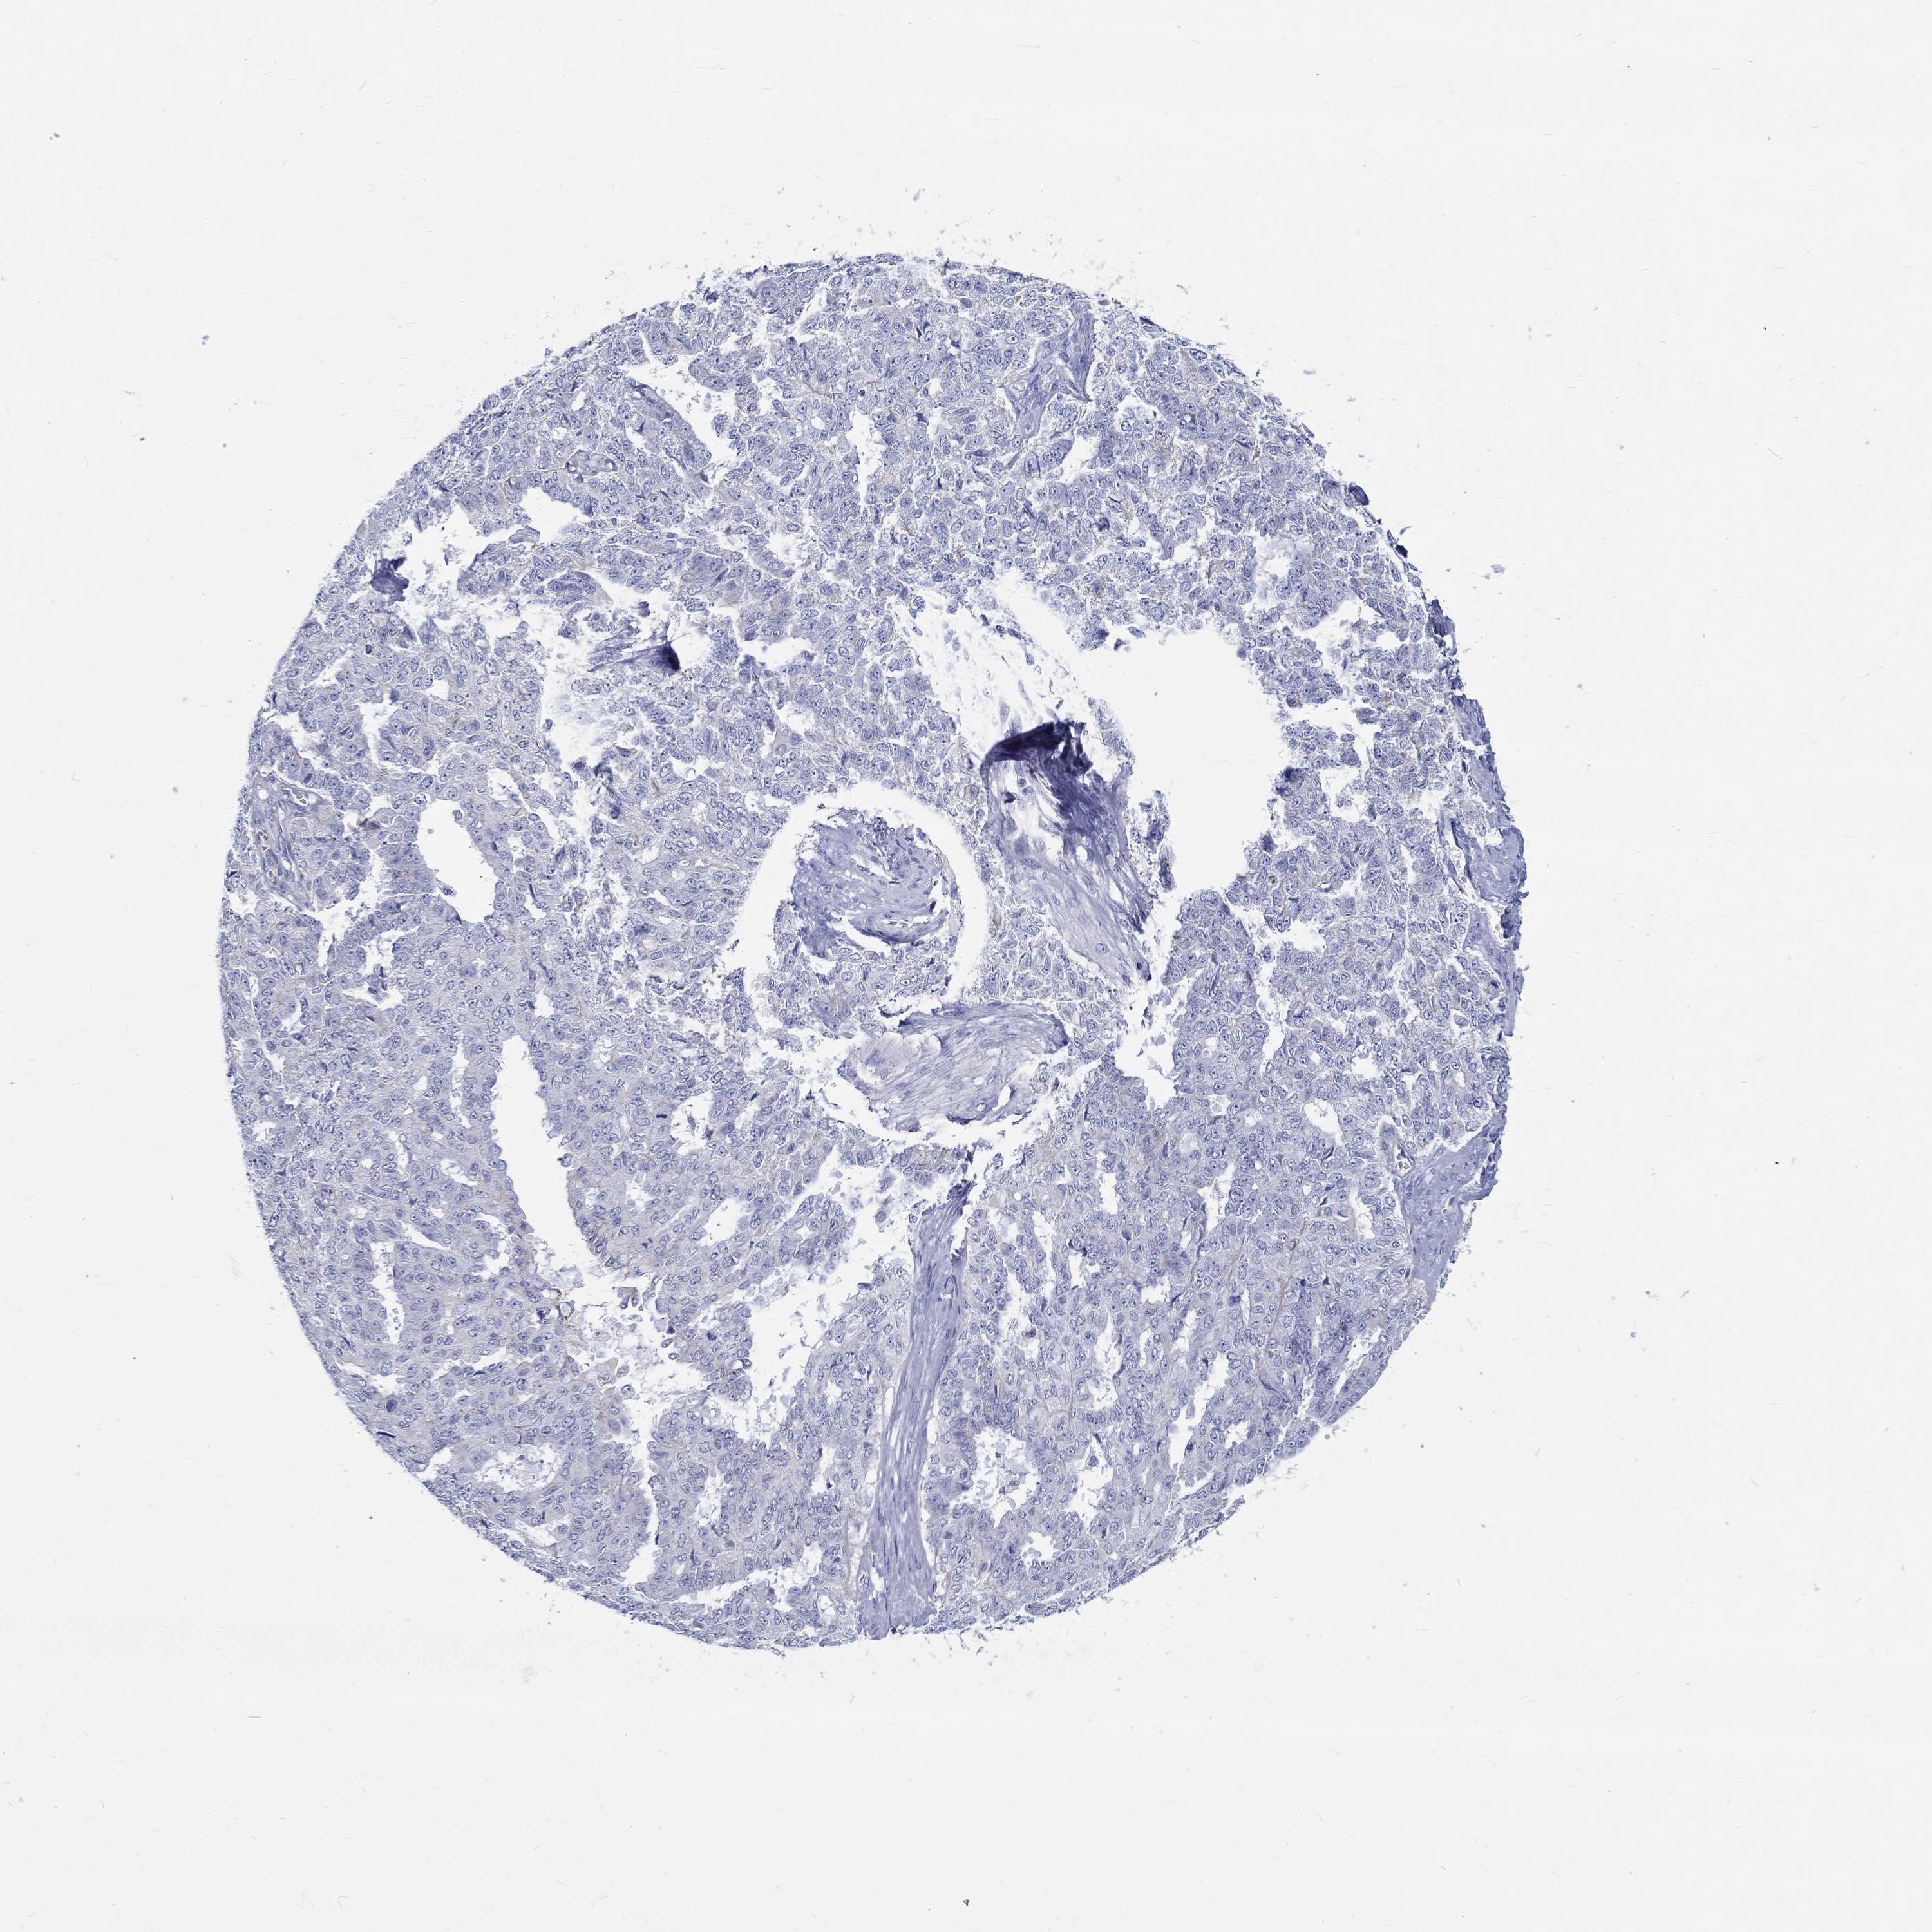

OVARIAN CANCER - Protein expressioni

A mouse-over function shows sample information and annotation data. Click on an image to view it in a full screen mode. Samples can be filtered based on level of antibody staining by selecting one or several of the following categories: high, medium, low and not detected. The assay and annotation is described here.

Note that samples used for immunohistochemistry by the Human Protein Atlas do not correspond to samples in the TCGA dataset.

Antibody stainingi

Antibody staining in the annotated cell types in the current human tissue is reported as not detected, low, medium, or high, based on conventional immunohistochemistry profiling in selected tissues. This score is based on the combination of the staining intensity and fraction of stained cells.

Each image is clickable and will lead to virtual microscopy that enables deeper exploration of all samples and also displays staining intensity scores, fraction scores and subcellular localization as well as patient and tissue information for each sample.

Antibody HPA076728

Staining

High

Medium

Low

Not detected

Intensity

Strong

Moderate

Weak

Negative

Quantity

>75%

75%-25%

<25%

None

Location

Nuclear

Cytoplasmic/membranous

Cytoplasmic/membranous,nuclear

Cystadenocarcinoma, serous, NOS

Cystadenocarcinoma, mucinous, NOS

Carcinoma, endometroid